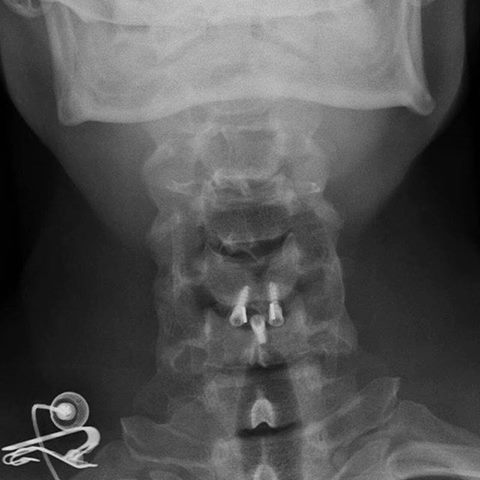

Taking x-rays at my doctors office today. Hope everything is still on the right spot;-)